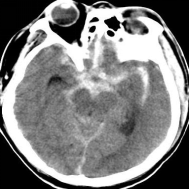

未破裂的脑动脉瘤的CT典型表现 破裂的脑动脉瘤 CT表现(SAH)